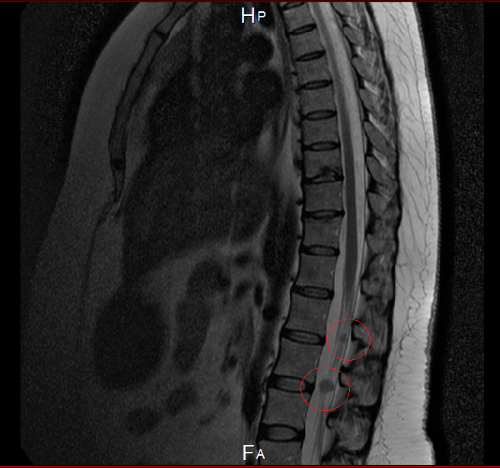

In this spring (spring appears to be a challenging season for myeloma), MRI revealed two neoplasms on the "cauda equina" (collection of nerves in the lower back). We are on our way to plan a treatment. Unfortunately, no one has seen such development of myeloma and it seems that we are experimenting. We have planned to undertake local irradiation of those two spots of neoplasms. Here is an image of the new tumors:

We have updated it a bit based on some private messaging with him to clarify the location of the new extramedullary tumors his wife has developed. The update includes a new image that gives a better sense of where the tumors are located.